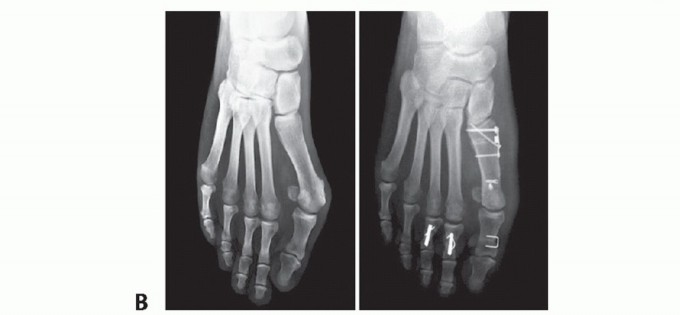

In our experience, the procedure reliably and reproducibly corrects the 1-2 IMA, HVA, and increased DMAA (FIG 5) and can be useful as a complementary procedure in severe cases (FIG 6).

FIG 5 • A. Preoperative and postoperative radiographic images of a right foot with hallux valgus with increased DMAA, treated by the biplanar chevron osteotomy. The correction of the DMAA and the sesamoid position is easy to see. The valgus of the great toe was also satisfactorily corrected. B. In these images, we can see the correction obtained with the biplanar distal chevron osteotomy. The cephalic fragment was 6 mm laterally dislocated to correct the IMA and the sesamoid position. The DMAA and HVA were corrected to normal values. In the lateral view, we can see the size and position of the screw used in the fragment fixation. C. Lateral views of a patient treated by the biplanar distal chevron osteotomy, where we can see both the plantar and dorsal arms of the osteotomy, the position of the screw used in its fixation, and the alignment of the cephalic fragment with the metatarsal diaphysis resulting from the dorsal fragment resection.

Usually due to inadequate Lateral translation

Rotation of the first metatarsal head

Soft tissue balancing during the capsulorrhaphy